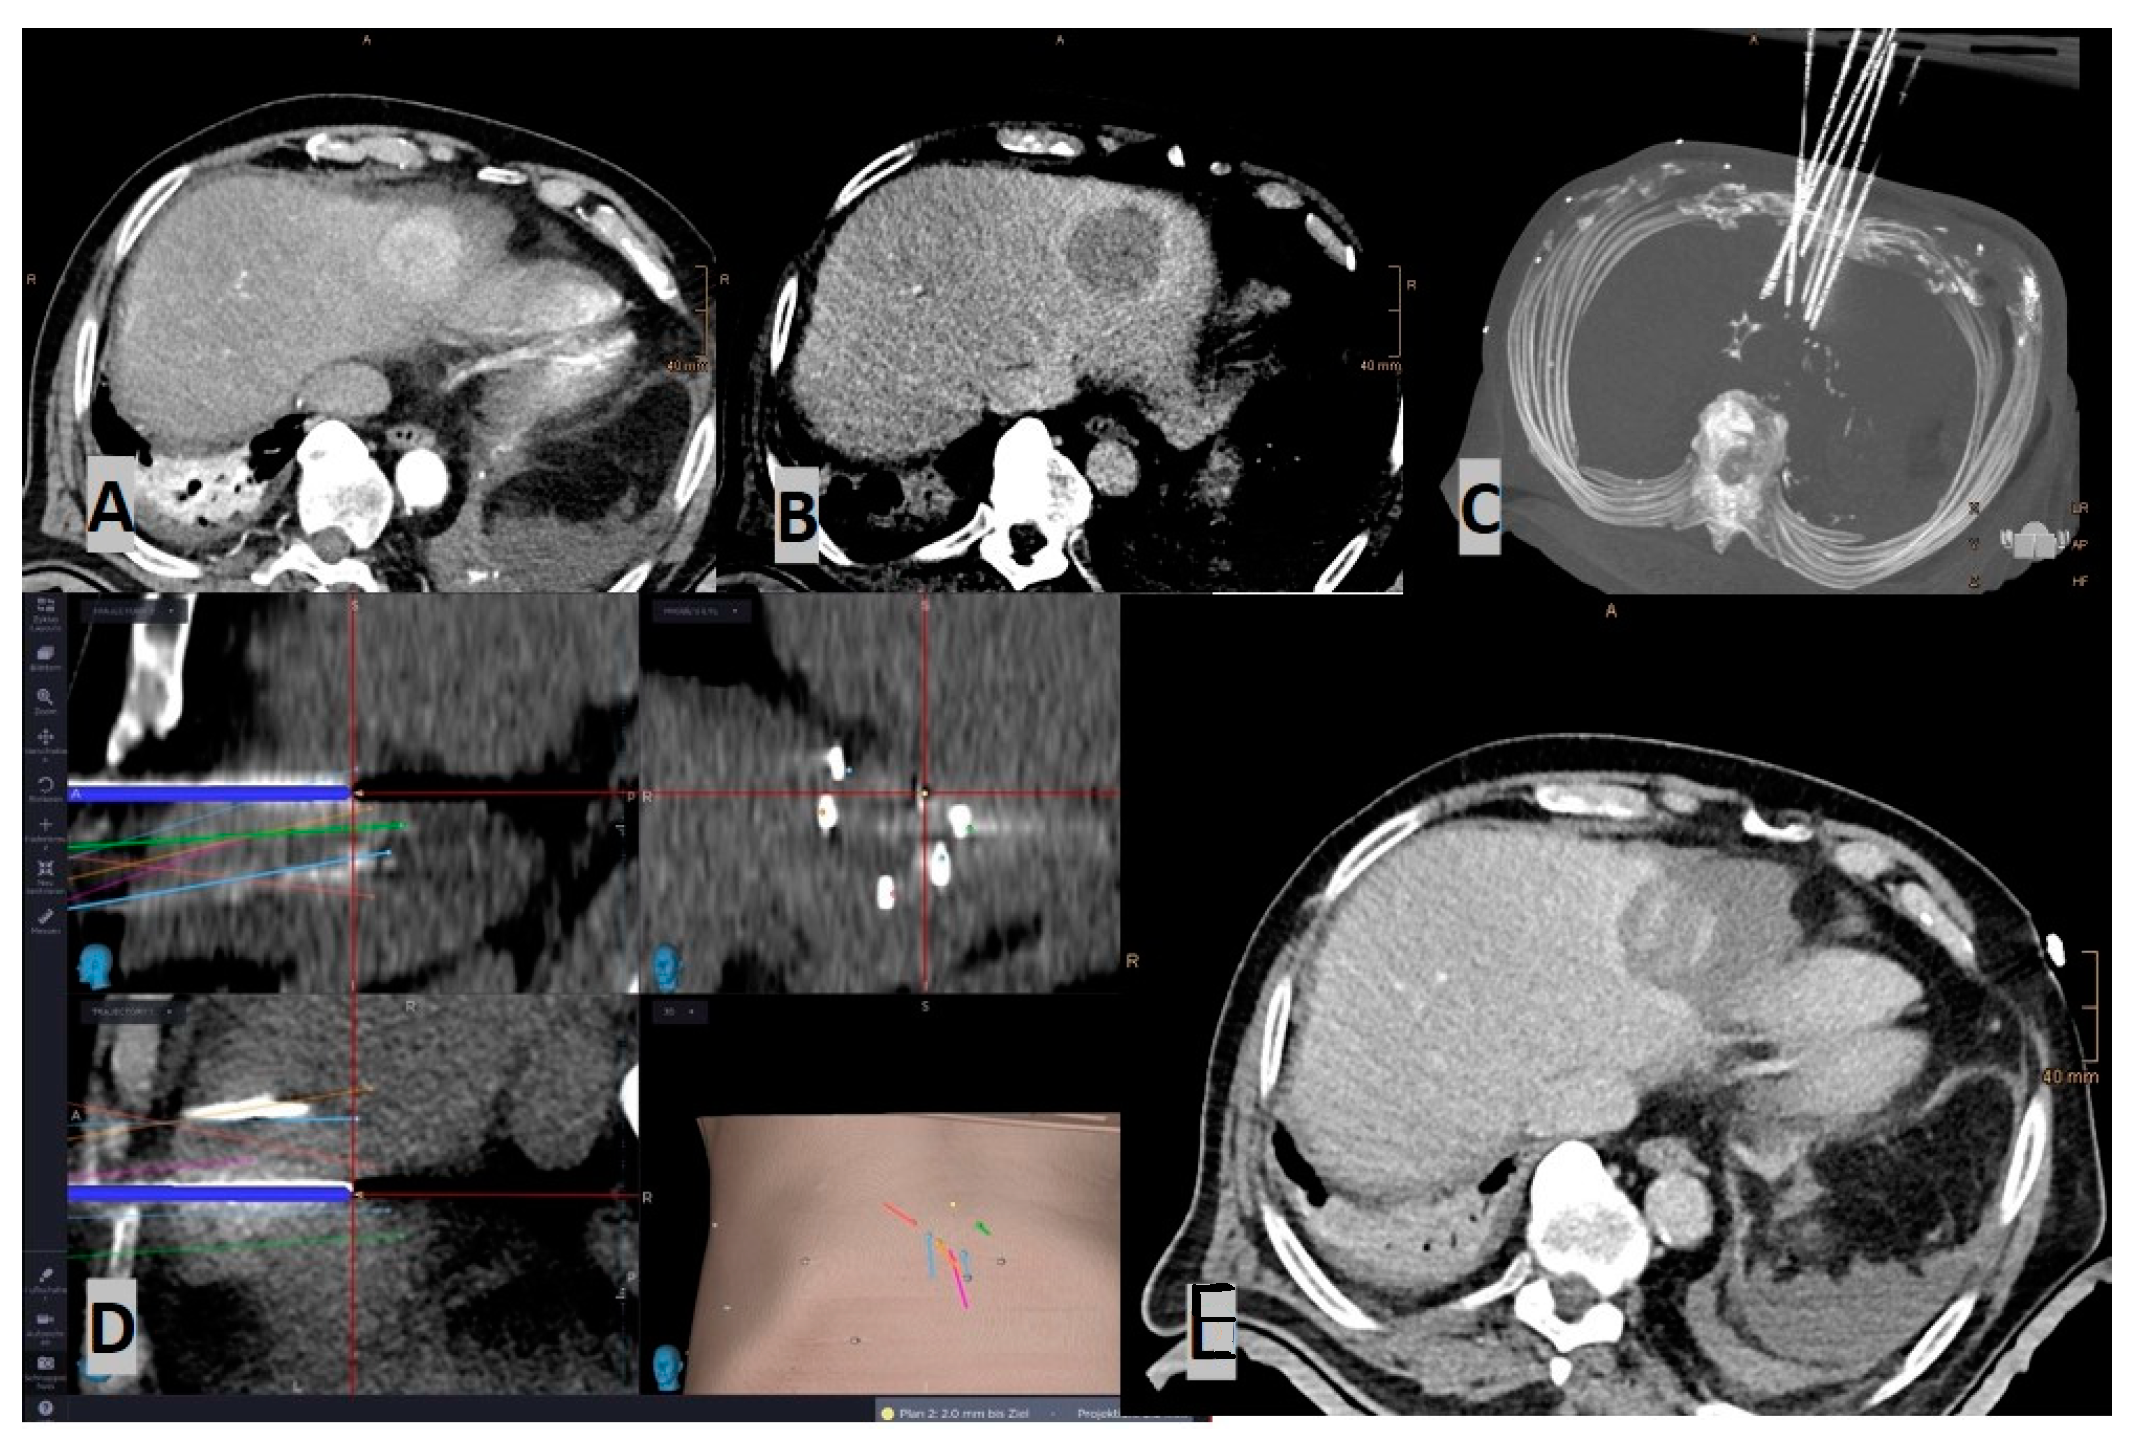

- Laimer, G.; Schullian, P.; Bale, R. Stereotactic Thermal Ablation of Liver Tumors: 3D Planning, Multiple Needle Approach, and Intraprocedural Image Fusion Are the Key to Success-A Narrative Review. Biology 2021, 10, 644. [Google Scholar] [CrossRef]

- Schullian, P.; Laimer, G.; Johnston, E.; Putzer, D.; Eberle, G.; Scharll, Y.; Widmann, G.; Kolbitsch, C.; Bale, R. Technical efficacy and local recurrence after stereotactic radiofrequency ablation of 2653 liver tumors: A 15-year single-center experience with evaluation of prognostic factors. Int. J. Hyperth. 2022, 39, 421–430. [Google Scholar] [CrossRef]

- Schullian, P.; Laimer, G.; Johnston, E.; Putzer, D.; Eberle, G.; Widmann, G.; Scharll, Y.; Bale, R. Reliability of Stereotactic Radiofrequency Ablation (SRFA) for Malignant Liver Tumors: Novice versus Experienced Operators. Biology 2023, 12, 175. [Google Scholar] [CrossRef]